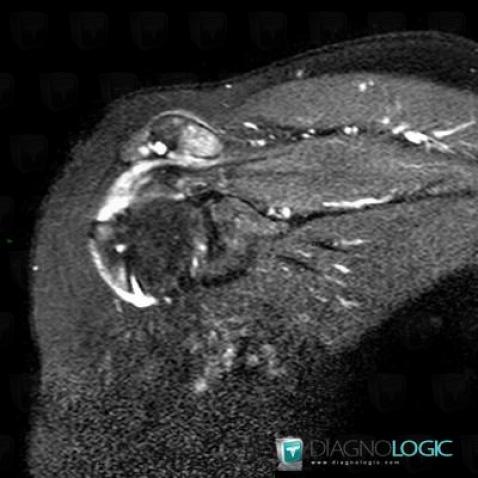

Rotator cuff tears, Supraspinatus tendon, MRI

Here is the specific information in the key image above:

- Diagnosis Rotator cuff tears, Location(s) Supraspinatus tendon, with gamuts